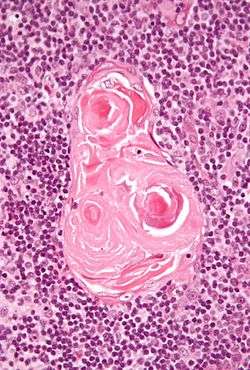

In the medullary portion, the network of reticular cells is coarser than in the cortex, the lymphoid cells are relatively fewer in number, and there are concentric, nest-like bodies called Hassall's corpuscles.These concentric corpuscles are composed of a central mass, consisting of one or more granular cells, and of a capsule formed of epithelial cells. They are the remains of the epithelial tubes, which grow out from the third pharyngeal pouches of the embryo to form the thymus.[4] Each follicle is surrounded by a vascular plexus, from which vessels pass into the interior, and radiate from the periphery toward the center, forming a second zone just within the margin of the medullary portion. In the center of the medullary portion there are very few vessels, and they are of minute size.